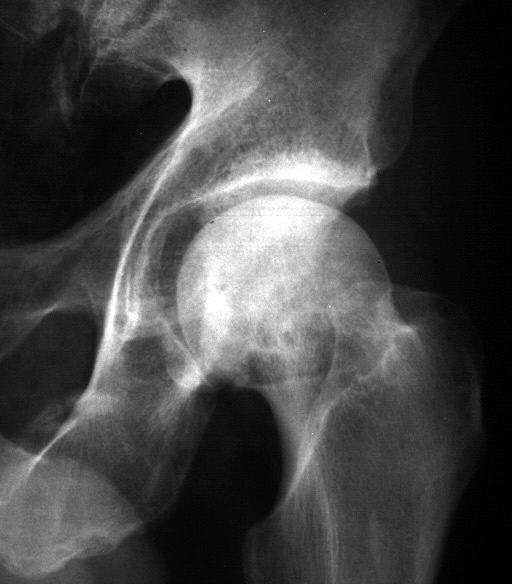

Secuencias Radiológicas

SE APRECIA UNA LINEA DE COLAPSO SUBCONDRAL EL SIGNO DE LA MEDIA LUNARADIOLOGIA NORMAL EL DIAG SE PUEDE REALIZAR POR RESONANCIA MAG

COLAPSO AFECTA LA SUPF SUBCONDRAL PERDIENDO SU MORFOLOGIA NORMAL

LA INCONGRUENCIA ARTICULAR PRODUCE PERDIDA DEL GROSOR DEL CARTILAGO Y CAMBIOS EN EL ACETABULO

RADIOLOGIA